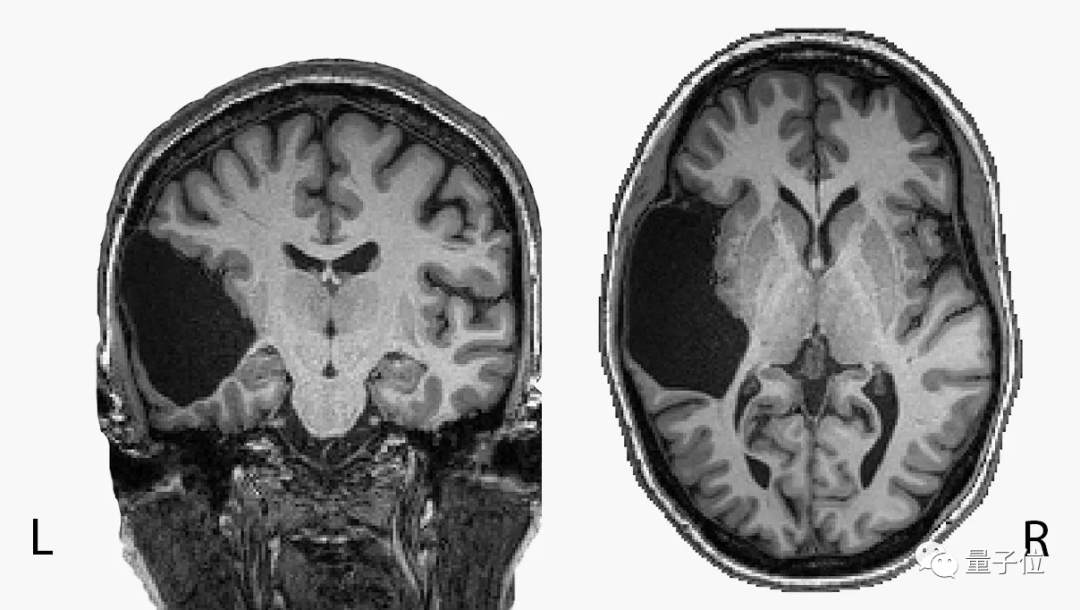

她活到25岁,才发现自己的左脑缺了一大块

本来应该是左颞叶(temporal lobe)的地方现在只有液体,另外脑干也不完整。

对于惯用右手的普通人来说,左颞叶正是承担语言理解功能的主要脑区。

同样惯用右手的她,语言能力非但没有受损,还在语言IQ测试中排进前2%。